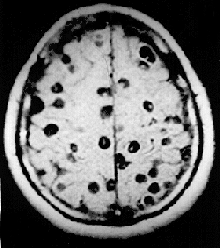

O Carter Center estimou que 200 milhões de pessoas, em 74 países, estão infestadas com o parasita causador da bilharziose, sendo que metade destas pessoas vivem na África sub-sariana. Apesar da condição ter uma baixa taxa de mortalidade, assume frequentemente um carácter de doença crónica que progressivamente danifica os órgãos internos do paciente. Pode influenciar negativamente o crescimento e o desenvolvimento cognitivo de crianças e aumentar significativamente o risco de cancro da bexiga em adultos. A doença é causada por diversas espécies do género Schistosoma, os quais podem perfurar a pele humana penetrando por essa via no corpo. As pessoas em maior risco são as que utilizam corpos de água infestados para recreio ou para lavagem de roupas.[34]

No ano 2000, estimava-se que 45 milhões de de pessoas estavam infestadas coma ténia Taenia saginata, originária de carne bovina infestada, e 3 milhões com a espécie Taenia solium, de origem suína.[38] A infecção do sistema digestivo por ténias adultas causa sintomas abdominais considerados desagradáveis e debilitantes, mas em geral não causam incapacidade ou ameaçam a vida.[39][40] A neurocisticercose, resultante da penetração de larvas de T. solium no sistema nervoso central, é a principal causa de epilepsia adquirida a nível global.[41] Em 2000, cerca de 39 milhões de pessoas estavam infectadas com tremátodes que na natureza parasitam peixes e crustáceos, mas que podem ser transmitidos aos humanos pela ingestão da peixe ou de crustáceos crus ou mal passados. A infecção de humanos pela espécie Diphyllobothrium latum, um parasita de peixes, causa difilobotríase da qual ocasionalmente resulta deficiência de vitamina B12 e, em casos severos, anemia megaloblástica.[38]